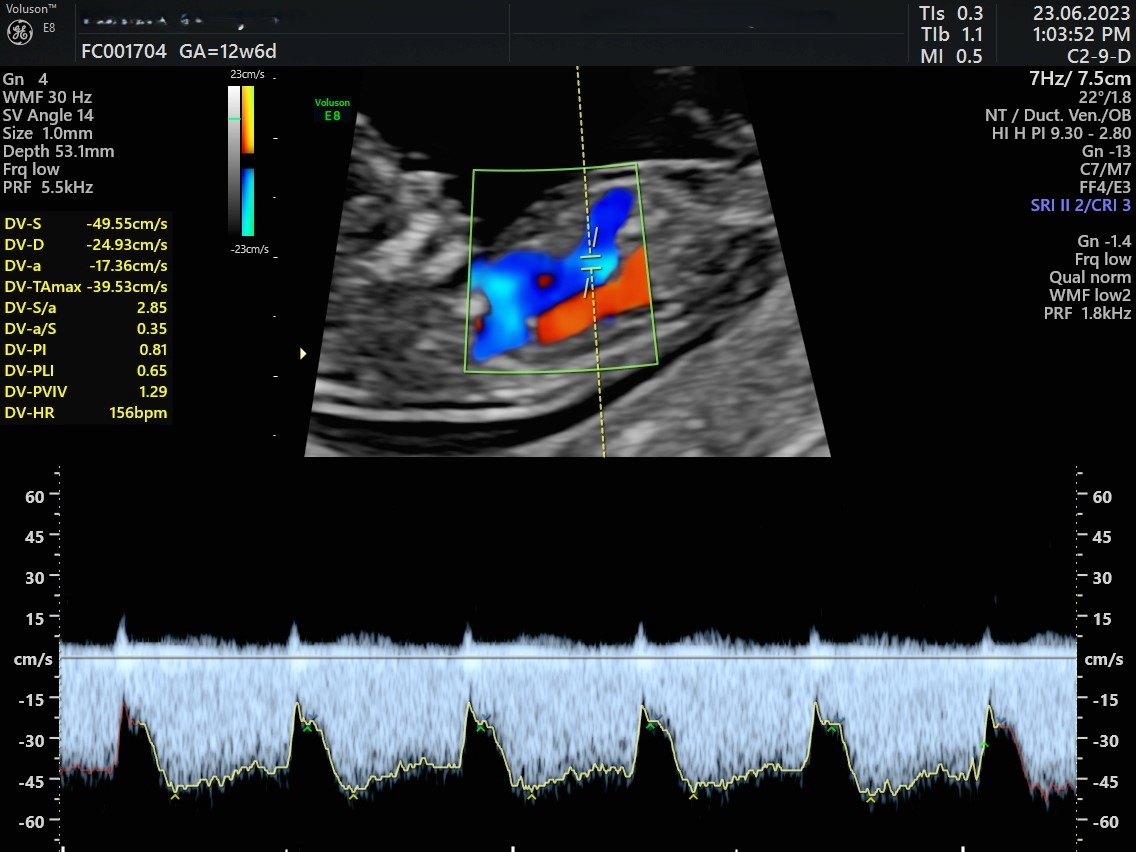

• Combined First trimester screening/ NT scan(+/

• Preterm preeclampsia screening)